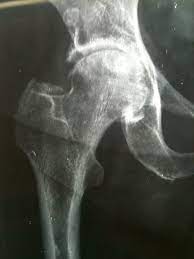

La diagnosi viene svolta attraverso un’accurata anamnesi ed esame clinico del paziente, infatti oltre alla valutazione della mobilità articolare, vi saranno dei test specifici che evocheranno il dolore articolare, i test di: Faddir e Faber (figure); fondamentali risulteranno anche delle radiografie del bacino e delle anche per valutare lo stato dell’articolazione. Una volta posta la diagnosi, in accordo con il paziente si pone l’indicazione all’intervento, che oggi in Italia è svolto in moltissimi nosocomi, sia pubblici che privati convenzionati SSN.